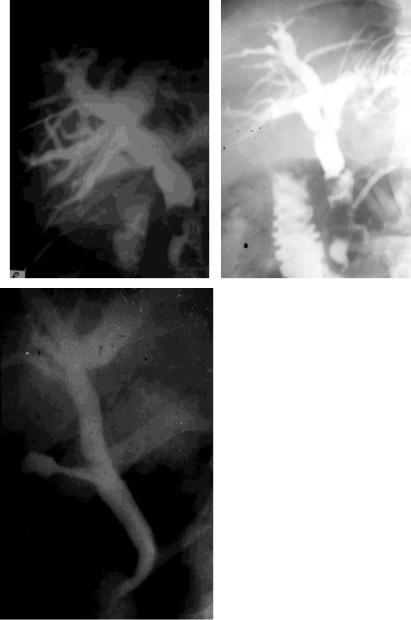

Рис. 47. Рентгенограммы при прямом контрастировании желчных протоков:

а - камень в желчном протоке (ЧЧХГ);

б - камень в желчном протоке (ЭРХГ);

в - стеноз большого дуоденального сосочка (операцион-

ная холангиография)

в

выводящей системы, то они используются у больных с механической непроходимостью желчных путей (при механической желтухе). В качестве контрастирующих препаратов применяются 25-30% растворы водорастворимых йодистых препаратов (кардиотраст, диодон, билиграфин, билигност и др.).

Чрескожная пункция органов желчевыводящей системы с последующим введением в них контрастного раствора может быть выполнена под лапароскопическим контролем

(чрескожная чреспузырная холецистохолангиография -

рис.46); под рентгенологическим или ультразвуковым кон-

тролем (чрескожная чреспеченочная холангиография -

рис.47, а). Прямое контрастирование внепеченочных желчных протоков возможно ретроградным введением в них контрастного раст-

Рис. 46. Чрескожная лапароскопическая холецистохолангиография:

а - схема; б - холецистохолангиограмма

вора при эндоскопическом исследовании двенадцатиперст-

ной кишки (эндоскопическая ретроградная холангиография -

рис.47, б).